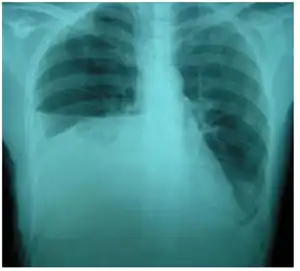

Urinothorax (pl. urinothoraces) is defined as urine in the fluid-filled cavity that surrounds the lungs.[1] It is usually caused by obstructive uropathy. It is mainly diagnosed by analyzing the pleural fluid. Treatment involves treating the underlying condition, which typically results in resolution of the urinothorax. It is an extremely rare cause of pleural effusion.[2]

| Right sided pleural effusion caused by urinothorax | |